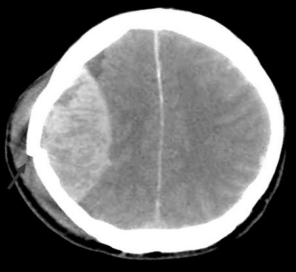

O trauma constitui uma das principais causas de mortalidade na Infância e adolescência, sendo o traumatismo crânio encefálico o trauma mais comum na infância.

Fonte: Disponível em: <https://www.clinicadralexandrecruzeiro.webnode.com.br/news> Acesso em: 18 nov. 2017.

Adolescente, 13 anos, vítima de atropelamento por carro, apresentou perda da consciência, logo após o trauma , mas ao chegar a equipe de resgate, a criança estava alerta, ECG de 14, apresentando intensa cefaleia e discreta hemiparesia à esquerda. Após 2 h na sala de emergência, apresentou rebaixamento do nível de consciência e piora neurológica. Foi submetida à TC de crânio de urgência.

De acordo com a imagem, o diagnóstico dessa criança é: